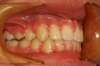

Intra Orale Droite